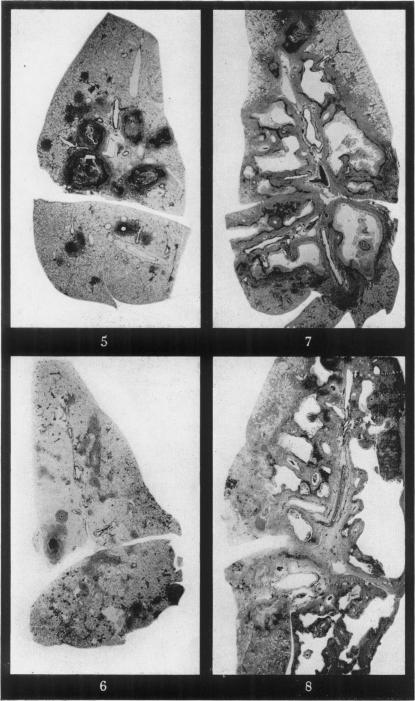

Experimental infective pneumoconiosis. III. Coal-mine dust and isoniazid-resistant tubercle bacilli of moderate virulence.

ZAIDI S H, HARRISON C V, KING E J, MITCHISON D A

Br J Exp Pathol. 1955 Dec;36(6):545-52.